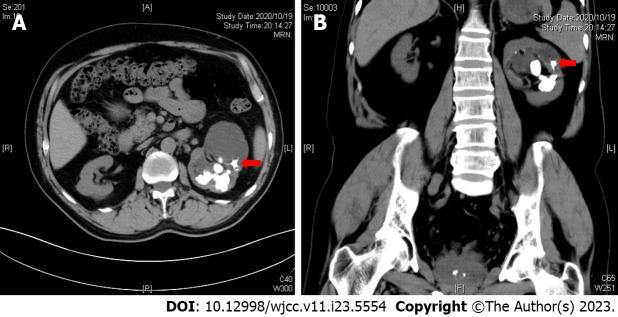

We report a 46-year-old man presenting with intermittent, painless gross hematuria and left flank pain. Urinary computed tomography revealed staghorn stones and secondary hydronephrosis. A jackstone with radiating branches was found in one of the dilated renal calyx. Percutaneous nephrolithotomy was performed and endoscopic images were recorded during the operation. Postoperative stone composition analysis revealed it as calcium oxalate monohydrate stones.

我们报告一名46岁男性,表现为间歇性、无痛性肉眼血尿和左侧腰痛。泌尿系统计算机断层扫描显示鹿角状结石和继发性肾积水。在一个扩张的肾盏中发现了一个带有放射状分支的鹿角状结石。进行了经皮肾镜取石术,并在手术过程中记录了内镜图像。术后结石成分分析显示其为一水草酸钙结石。